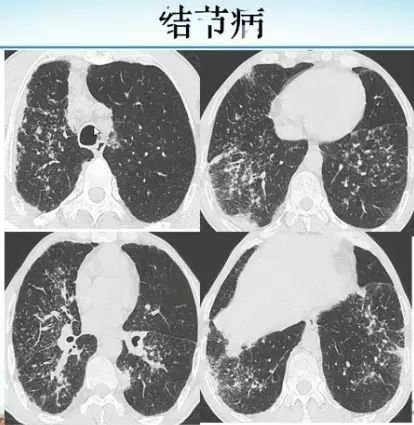

肺内“烟花征”,为活动性肺结核的CT表现之一。是结核经支气管播散并由多发小叶中央结节堆积而成,形态特征似烟花在空中散开。病理基础为细支气管及肺泡内干酪坏死性肉芽肿。